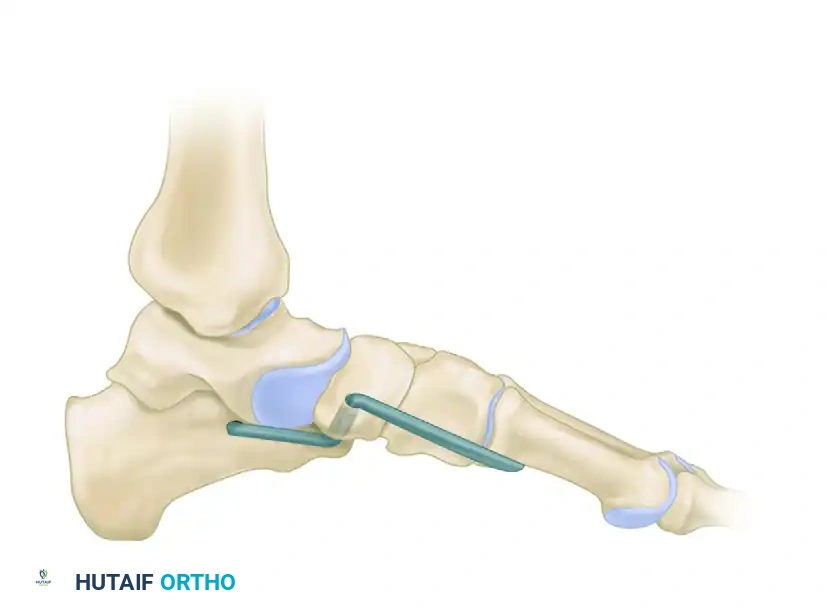

5. Graft Insertion and Alignment Assessment

- Harvest or prepare the appropriately sized tricortical graft (typically 8 to 10 mm wide at its lateral base, tapering medially to fit the wedge defect).

- Insert the graft into the distracted osteotomy. The cortical margin of the graft should sit flush with the lateral wall of the calcaneus.

- Critical Step: Assess the foot for clinical and radiographic alignment before final fixation. Ensure the heel is in neutral to slight valgus and the forefoot abduction is corrected.

- Do not overcorrect. Overcorrection leads to a rigid, supinated forefoot and severe lateral column overload, which is poorly tolerated by the patient.

6. Fixation

- Fix the graft securely to prevent displacement or collapse.

- Options include:

- Smooth or threaded Steinmann pins (often buried beneath the skin).

- Bone staples.

- A cervical H-plate or dedicated lateral column locking plate.

- Note: The subcutaneous nature of hardware in this region frequently causes irritation, necessitating hardware removal at a later date. Discuss this possibility with the patient preoperatively.